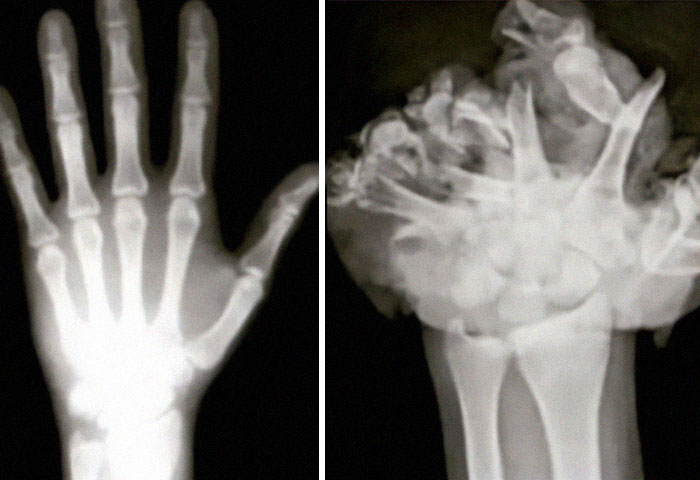

Reconstrucción de paladar y labio leporino doble